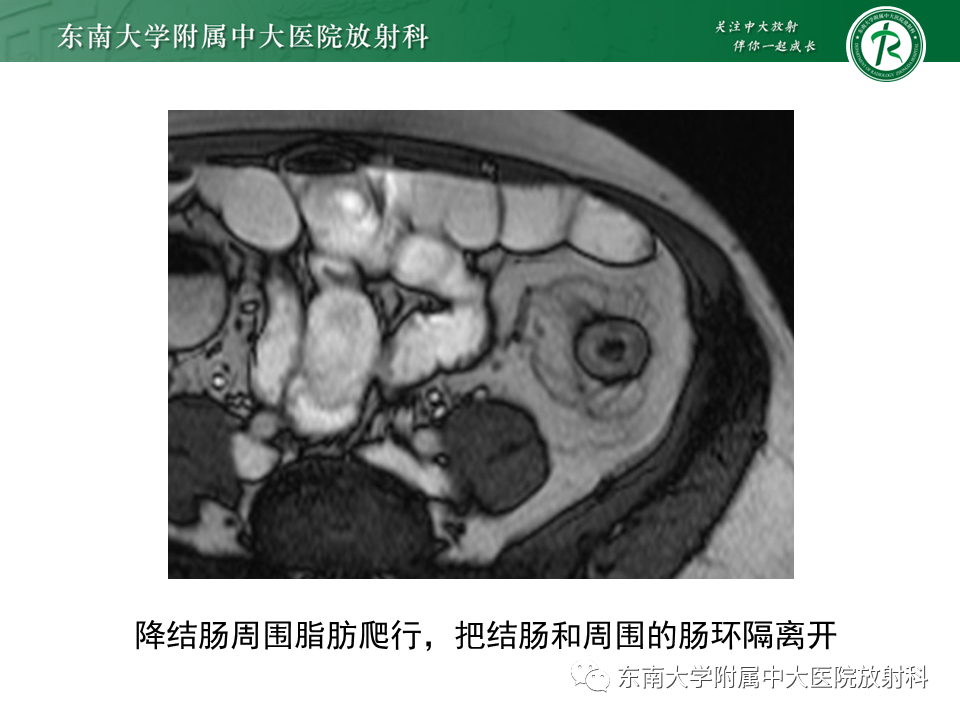

克罗恩病